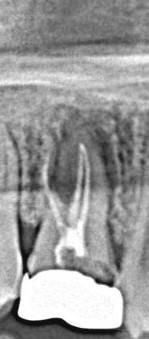

안녕하세요, 5년전에 군대에서 (군병원 X, 양구 시내 치과) 크라운을 했었는데. 3일전 운동할때부터 갑자기 씹을때마다 통증이 느껴지더라구요 ! 그래서 오늘 치과를 방문해서 엑스레이를 촬영하고 상담을 했는데 , 무조건 발치를 하고 임플란트를 하셔야 한다 하더라구요. 그래서 질문을 드리려고 왔습니다 ! (( 오른쪽 위 어금니 입니다 ! ))

• 1번 째 사진

1. 엑스레이 보면 크라운 안쪽이 다 썩어서 삭은 상태입니다 치아 살리기는 어려울 것 같습니다 다만 발치 전 크라운 제거하고 치아 상태 한번 체크해볼 순 있습니다

1. 지금 사진으로 보아서는 발치를 해야할 정도로 염증이 심해보입니다. 다만 무조건 임플란트라기 보다는 dental-ct 등을 촬영하여 재신경치료 가능성이 있는지 판단해보아야 합니다. 재신경치료 가능하다면 해보는 것도 한 방법이며 재신경치료가 불가능하다면 발치 후 임플란트를 해야 합니다.